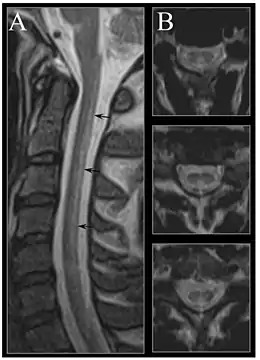

Early changes include a spongiform state of neural tissue, along with edema of fibers and deficiency of tissue. The myelin decays, along with axial fiber. In later phases, fibric sclerosis of nervous tissues occurs. Those changes occur in dorsal parts of the spinal cord and to pyramidal tracts in lateral cords and is called subacute combined degeneration of spinal cord.[105] Pathological changes can be noticed as well in the posterior roots of the cord and, to lesser extent, in peripheral nerves.

MRI of the brain may show periventricular white matter abnormalities. MRI of the spinal cord may show linear hyperintensity in the posterior portion of the cervical tract of the spinal cord, with selective involvement of the posterior columns.